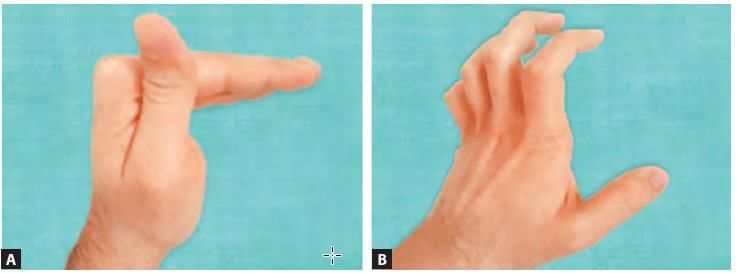

Hand deformity presenting as hyper-extension at the metacarpo-phalangeal joint and flexion at inter-phalangeal joint, occurs due to paralyzed: (NEET-PG 2020p)